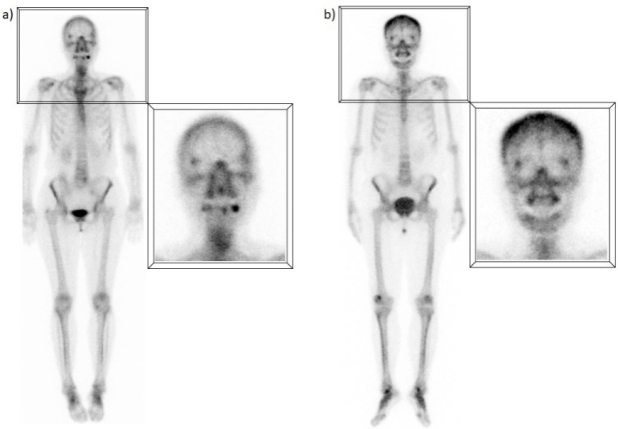

A) Captación difusa en huesos frontales

La hipercaptación difusa y simétrica en los huesos frontales suele ser secundaria a hiperostosis, definida como un crecimiento benigno excesivo de la tabla interna de los huesos frontales y, en algunos casos, parietales. Aunque se creía relacionada con trastornos hormonales, actualmente su etiología no está completamente clara. Se presenta en el 5 - 12% de la población, siendo más común en mujeres adultas mayores. Suele ser un hallazgo incidental sin significado patológico, aunque puede estar asociado a condiciones como diabetes, enfermedad tiroidea, virilismo y acromegalia, entre otras(1,2) (fig. 1).